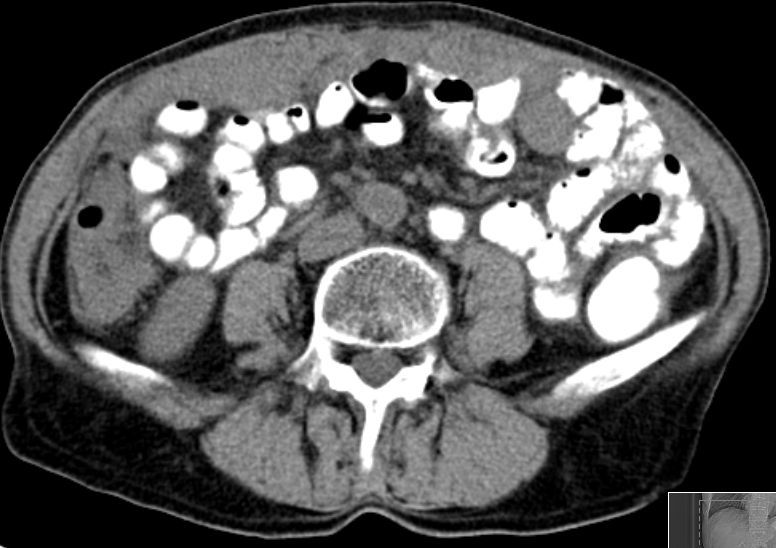

CT |

75-jährige Frau mit beiderseitigem Ovarial-Karzinom.

Ausgeprägte infiltration des Netzes und des Peritoneums.